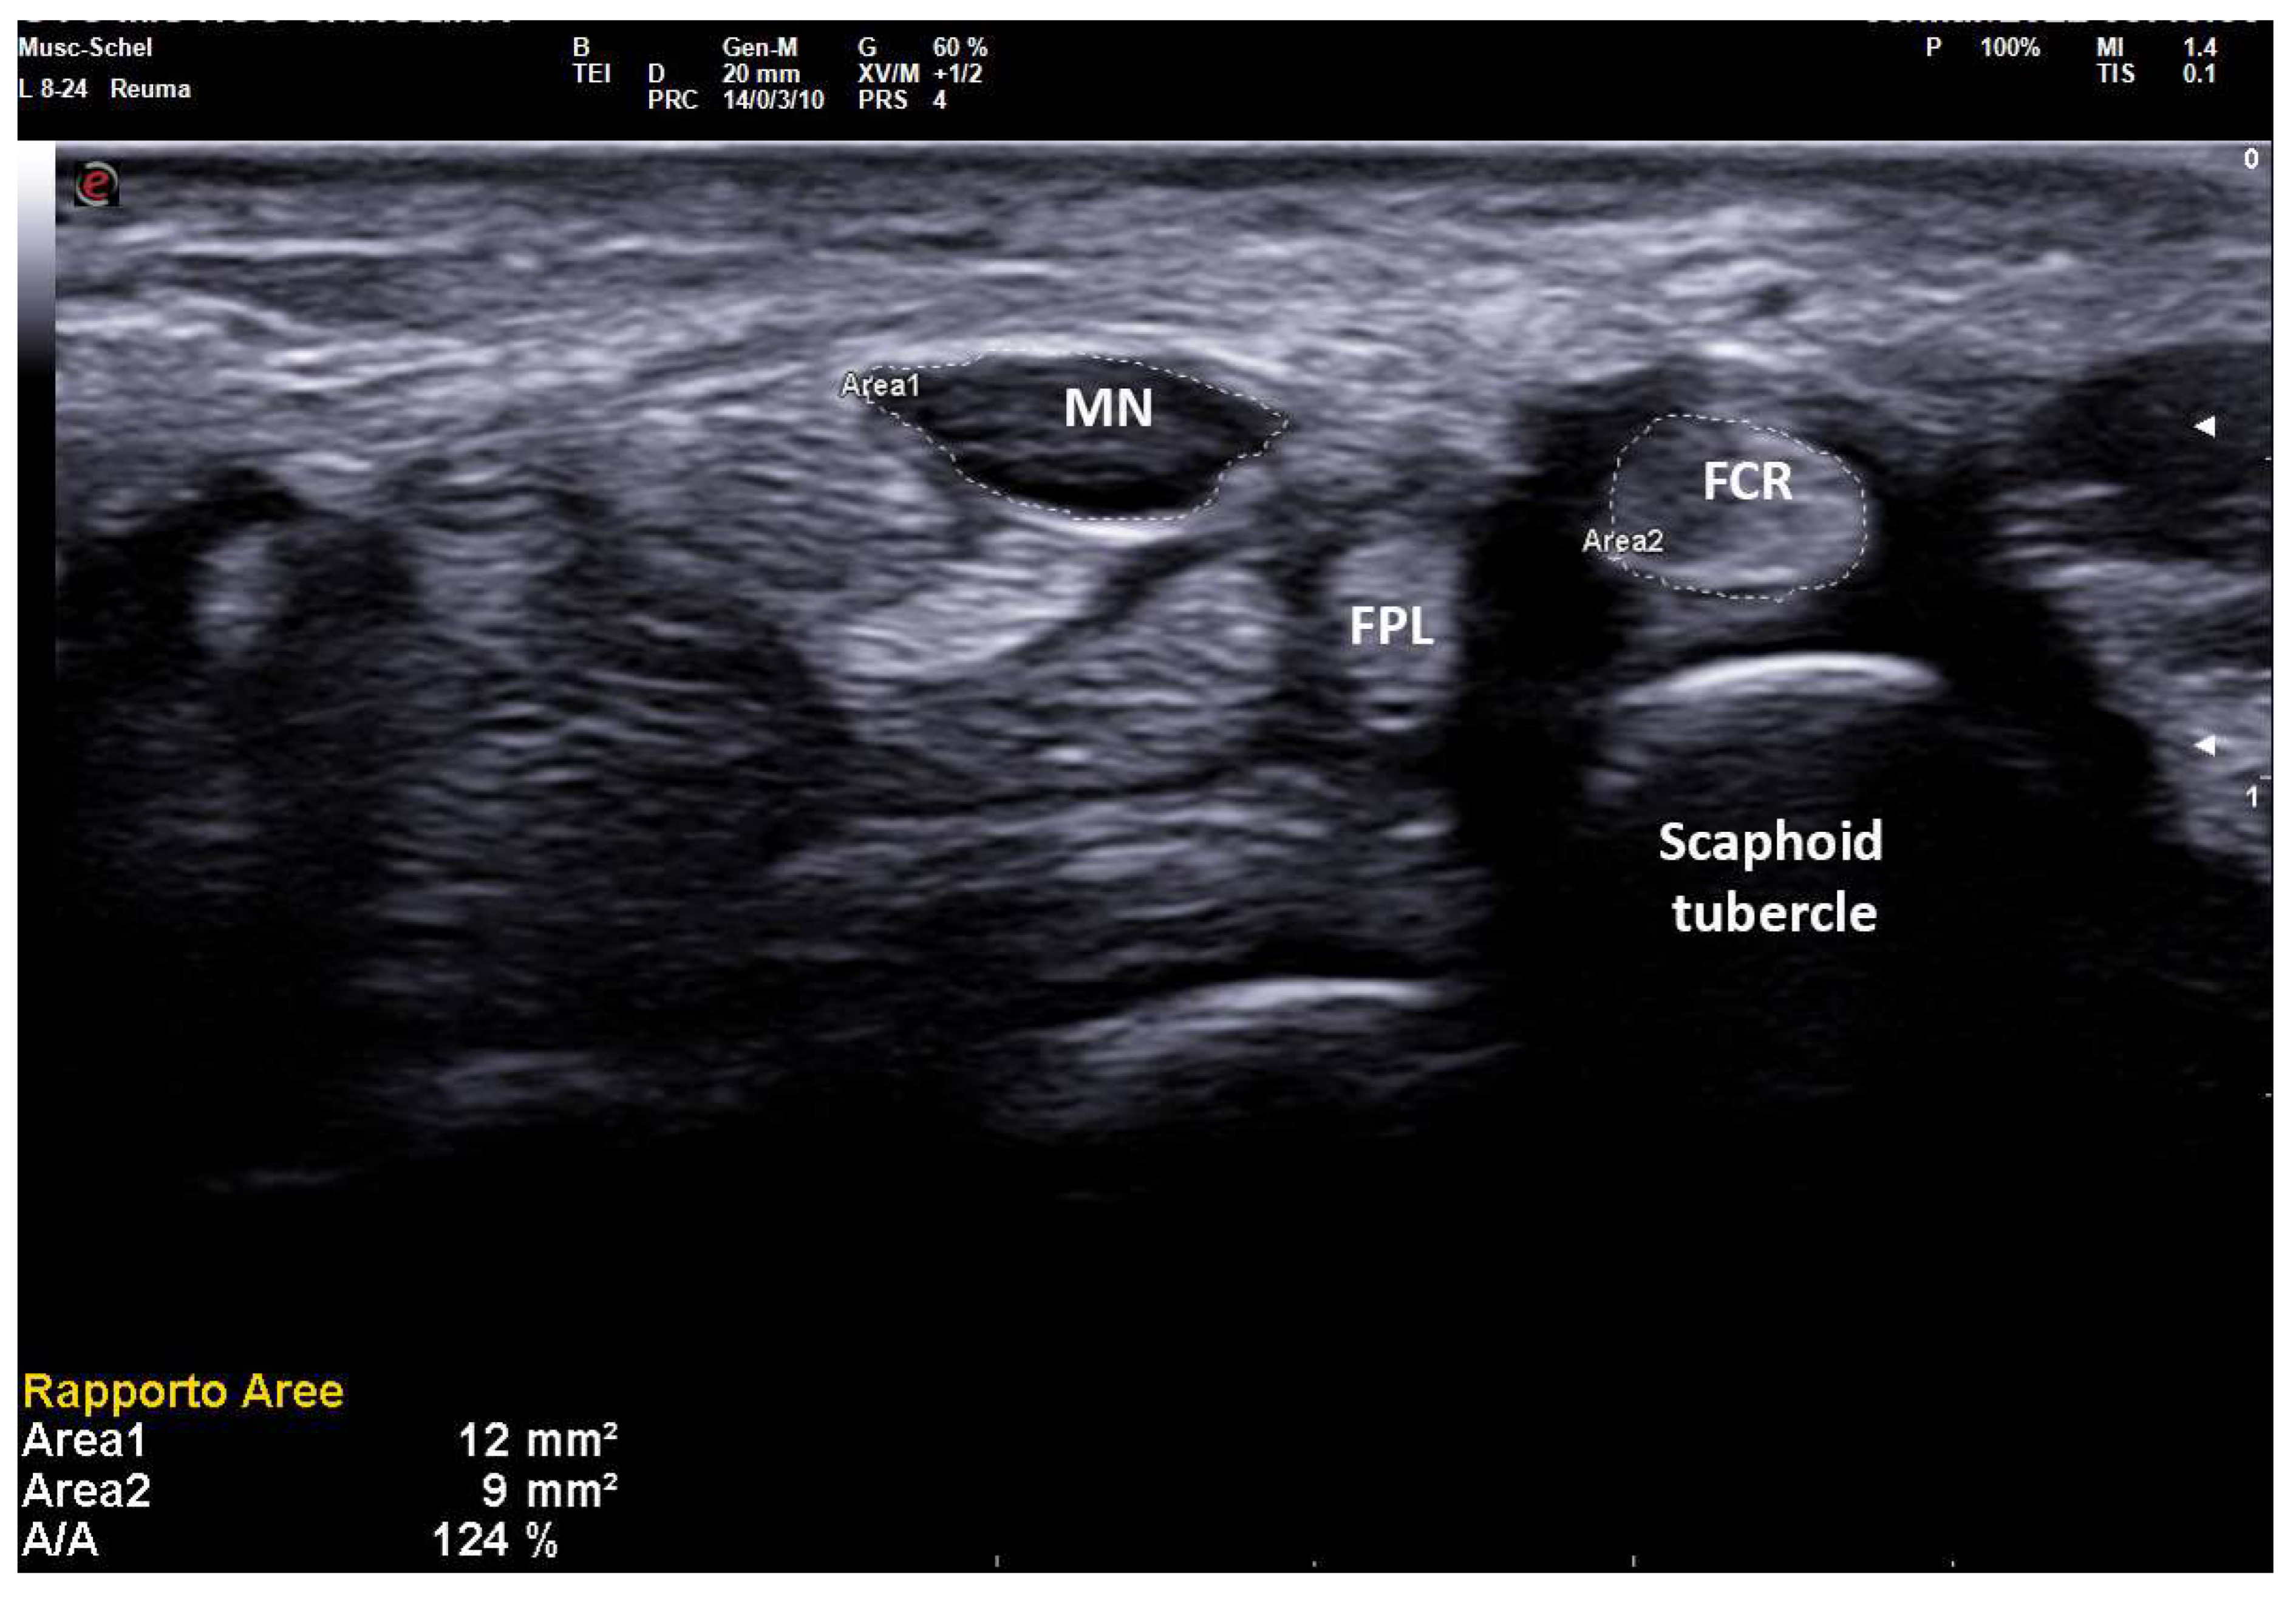

As reported in previous studies [11] MN-CSA is strongly influenced by anthropometric factors in healthy subjects, but in pathologic wrists, the importance of anthropometric parameters is reduced as MN-CSA variability also depends on the severity of neuropathic swelling. Nevertheless, in conditions of anthropometric extremes, large normal nerves or small pathologic nerves could constitute a false positive or false negative in US examination. Even if both crude MN-CSA and NTR showed good correlations with SCV, DML, and finally with PS, in a generic population we demonstrated the superiority of NTR when patients were stratified according to anthropometric extremes. Particularly, in patients taller than 175 cm and shorter than 156 cm, NTR maintained an excellent correlation with PS, while such correlation was lacking for MN-CSA (Figure 5).

Figure 5.

Transverse scan over right carpal tunnel in a small female patient (150 cm × 50 kg, 13.7 cm of wrist circumference) affected with medium-grade CTS (Padua Scale 3, SCV 37.1 m/sec, DML 4.8 ms). Linear 8–24 MHz probe. Both areas of median nerve (MN) and flexor carpi radialis (FCR) were manually traced. A MN-CSA of 12 mm2 is not always considered pathologic (cut-off for MN neuropathy until 14–15 mm2 in some studies on CTS) and the severity is often underestimated because of the anthropometric characteristics of the patient. The NTR shows values unequivocally pathologic (124%), as MN-CSA is compared with an anatomic structure (FCR-CSA) that maintains small dimensions in CTS, following the anthropometric characteristics of the patient.